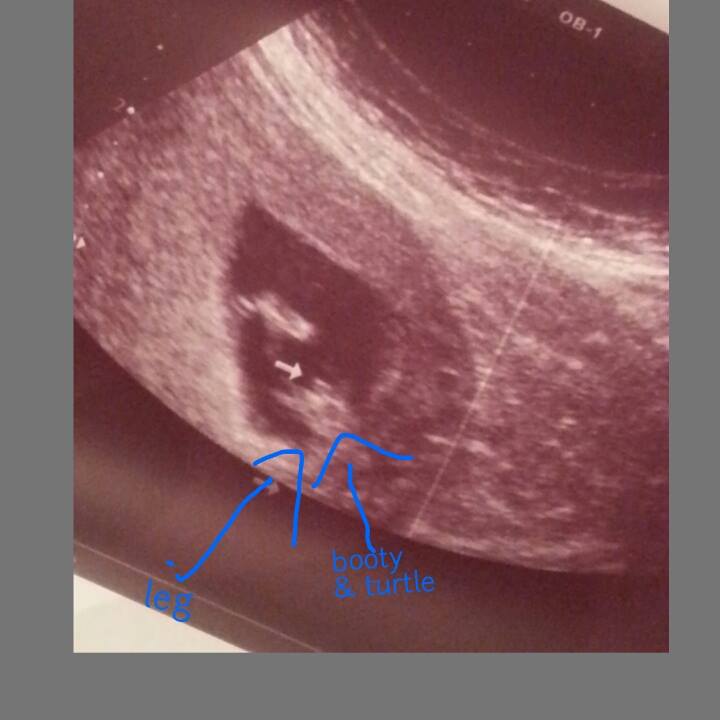

HELPPPP... Have been told: BOY (14wks), BOY (16wks), GIRL(17wks), & GIRL (18wks)

HELPPPP... Have been told: BOY (14wks), BOY (16wks), GIRL(17wks), & GIRL (18wks)!!

Absolutely completely confused & upset. A tech friend who works at our local hospital (so not an OB tech that views gender everyday, but does has experience & has been doing them for years) has been performing ultrasounds for me just out of excitement herself. I've so appreciated being able to watch my baby grow as I am high risk, & it keeps my mind at ease! BUT gender predictions have been a nightmare thus far. My latest just doesnt seem like normal "girl parts" to me. It is protruding far more than what I have seen on my two previous girls. The base of the the "three lines" isnt even attached at the bottom of the baby. Its odd to say the least. But some opinions will be greatly appreciated. My actual OB will be doing a gender u/s next week at 21 weeks so hopefully we will get some clarity. Regardless I feel like I will have a hard time trusting it & getting to bond with my SON or DAUGHTER :( ... hellllpAttachment 31823